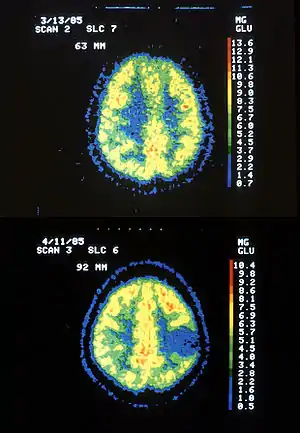

| Two PET images—the upper of which shows a normal brain and the lower shows astrocytoma. | |